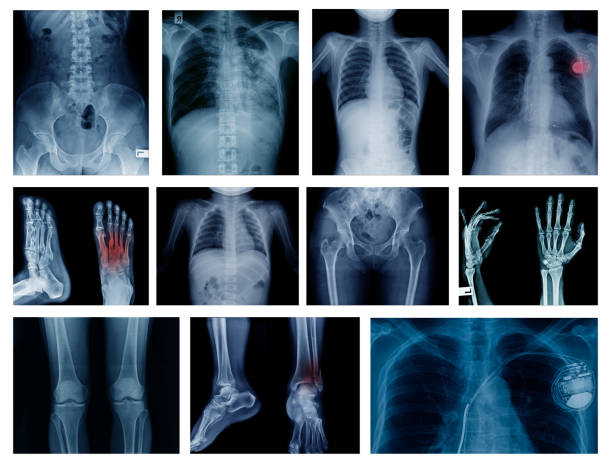

A fracture is a break, most often in a bone. An open or complicated fracture occurs when a shattered bone punctures the skin. Fractures are usually caused by vehicle accidents, falls, or sports injuries. Low bone density and osteoporosis are two more reasons for bone weakness. Stress fractures, which are extremely minute fissures in the bone, can be caused by overuse.

Fracture symptoms include:

• Excruciating agony

• Deformity – the limb appears to be out of position

• Swelling, bruising, or discomfort in the area of the injury

• Tingling and numbness

• Having difficulty moving a limb